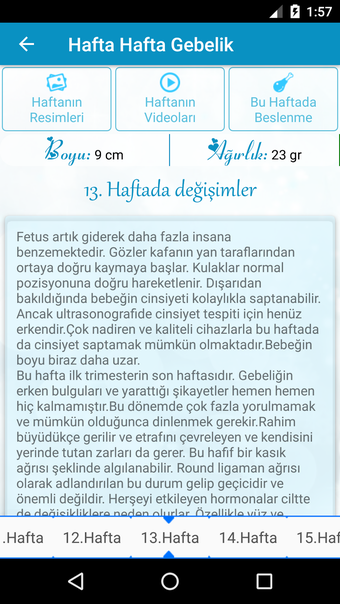

Hamilelik Takibi is an Android application created by HokkabazSoft that offers a simple and comprehensive way to track your pregnancy. It provides detailed information about each week of pregnancy and offers nutritional tips to ensure a healthy pregnancy. You can also track your baby's height and weight, watch videos of the baby in the womb, and ask and answer questions on a platform for other users. With the aid of specialists, the Hamilelik Takibi app has collated women's accounts of their 40-week pregnancies. You may view an ultrasound or 3D drawings of your developing child every week and receive weekly updates on their progress. Monthly updates for the next 9 months are also shown for your perusal. The information in the app has been compiled from many sources (including the internet and professionals) and is provided to you as an average. Therefore, it is suggested that you do not follow the advice in the application without visiting your doctor since it may not give you the real values of your kid. In sum, Hamilelik Takibi is a powerful tool for monitoring pregnancy and learning how to have a healthy baby.